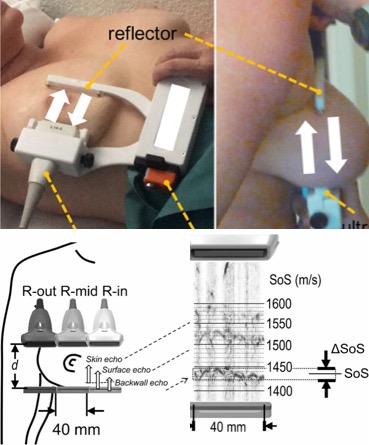

[2022] Bhaskara Rao Chintada, Richard Rau, and Orcun Goksel:

"Spectral Ultrasound Imaging of Speed-of-Sound and Attenuation Using an Acoustic Mirror",

Frontiers in Physics 10(860725), May 2022.

[2022] Bhaskara Rao Chintada, Richard Rau, and Orcun Goksel:

"Spectral Ultrasound Imaging of Speed-of-Sound and Attenuation Using an Acoustic Mirror",

Frontiers in Physics 10(860725), May 2022.

[2019] Sergio J. Sanabria, Marga B. Rominger, and Orcun Goksel:

"Speed-of-Sound Imaging Based on Reflector Delineation",

IEEE Trans Biomedical Engineering 66(7):1949-1962, Jul 2019.

[2019] Sergio J. Sanabria, Marga B. Rominger, and Orcun Goksel:

"Speed-of-Sound Imaging Based on Reflector Delineation",

IEEE Trans Biomedical Engineering 66(7):1949-1962, Jul 2019.